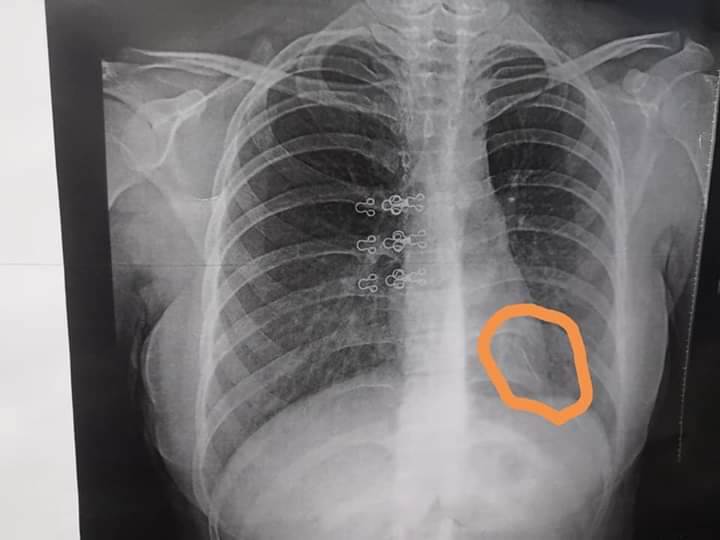

تمكن فريق قسم جراحة القلب والصدر بمستشفى بنها الجامعى، من إجراء جراحة شق صدري محدود لاستخراج دبوس لفتاة عشرينية ابتلعته في حفل خطوبتها واستقر بالرئة اليسرى بجوار القلب مباشرة بعد أن استنشقته بالفم بطريق الخطأ من شهرين في حفل خطوبتها.

وأضاف الجزار، أن الفتاة وتوجهت خلال الشهرين الماضيين لمستشفى شبين الكوم الجامعي ومعهد الكبد بشبين ومستشفى الدمرداش، وفشلت كل محاولات استخراج الدبوس بالمنظار، مشيرا إلى أن الفتاه خرجت بصحة جيدة.